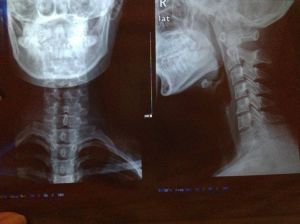

正常頸椎生理曲度從側方看人體在端坐或站立時的頸部似乎是直的,其實包繞於內的頸椎並不是直的,而是在其中段有一向前凸出的弧度。在醫學上把這一向前的弧形凸起稱為頸椎的生理曲度。通過X線片上的頸椎顯像:沿此曲度走行,在各個頸椎椎體後緣都有形成的連續 、光滑的弧形曲線,醫學上稱之為頸椎曲度。當長時間不正確的坐姿、或是長時間的勞累、頸椎缺少活動、脊柱損傷、脊柱鈣化等就會導致頸椎生理曲度變直。

頸椎生理曲度的存在,能增加頸椎的彈性,減輕和緩衝重力的震盪,防止對脊髓和大腦的損傷。由於長期坐姿、睡姿不良和椎間盤髓核脫水退變時,頸椎的前凸可逐漸消失,甚至可變直或呈反張彎曲,即向後凸,成為頸椎病X線上較為重要的診斷依據之一。

具有頭、肩、頸、臂的疼痛及相應的壓痛點,X線片上沒有椎間隙狹窄等明顯的退行性改變,但可以有頸椎生理曲線的改變,椎體間不穩定及輕度骨質增生等變化。此型在臨床上極為常見,是最早期的頸椎病。由於症狀較輕,往往重視不夠,以致反覆發作使病情加重,不少反覆落枕的病人即屬於此種改變。從大量的臨床觀察證實,此型實際上是頸椎病的最初階段,也是治療最為有利的時機。